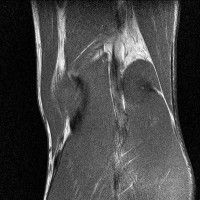

무릎 mri 간단히 봐주실 수 있으시나요 ㅠㅠ

안녕하세요 8년전 십자인대 수술하고 최근 무리한 운동에 무릎 불편감이 생겨서

mri 찍었습니다.

진단결과는 첫 찍은 병원에서 활액막염 이라는 진단을 받았습니다. 혹시 봐주실 수 있으실까요?

올라온 MRI가 단편적이라서 정확한 진단에 어려움이 있지만 십자인대에는 큰 이상이 있지는 않은것 같으며, 무릎관절내 물이 있는 것으로 보아 활액막염의 진단이 맞을 것 같습니다.

하지만 단편적인 영상이기 때문에 촬영병원에서 정확한 판독지 등을 받으시는 것이 좋겠습니다.